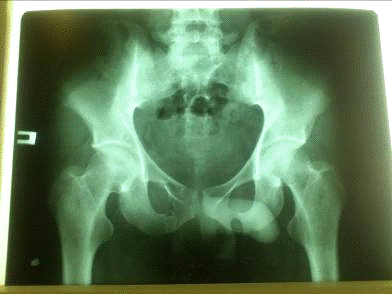

На рентгенограмме костей таза в прямой проекции - перелом обеих ветвей правой лобковой кости со смещением отломков.

На рентгенограмме: перелом лучевой кости с тыльным смещением, перелом обеих ветвей правой лобковой кости со смещением отломков